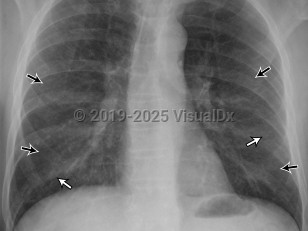

Chest pain, Pleural effusion, 50-59 year old Female

Pleural effusionPleural effusion

Hemothorax

Pulmonary empyema